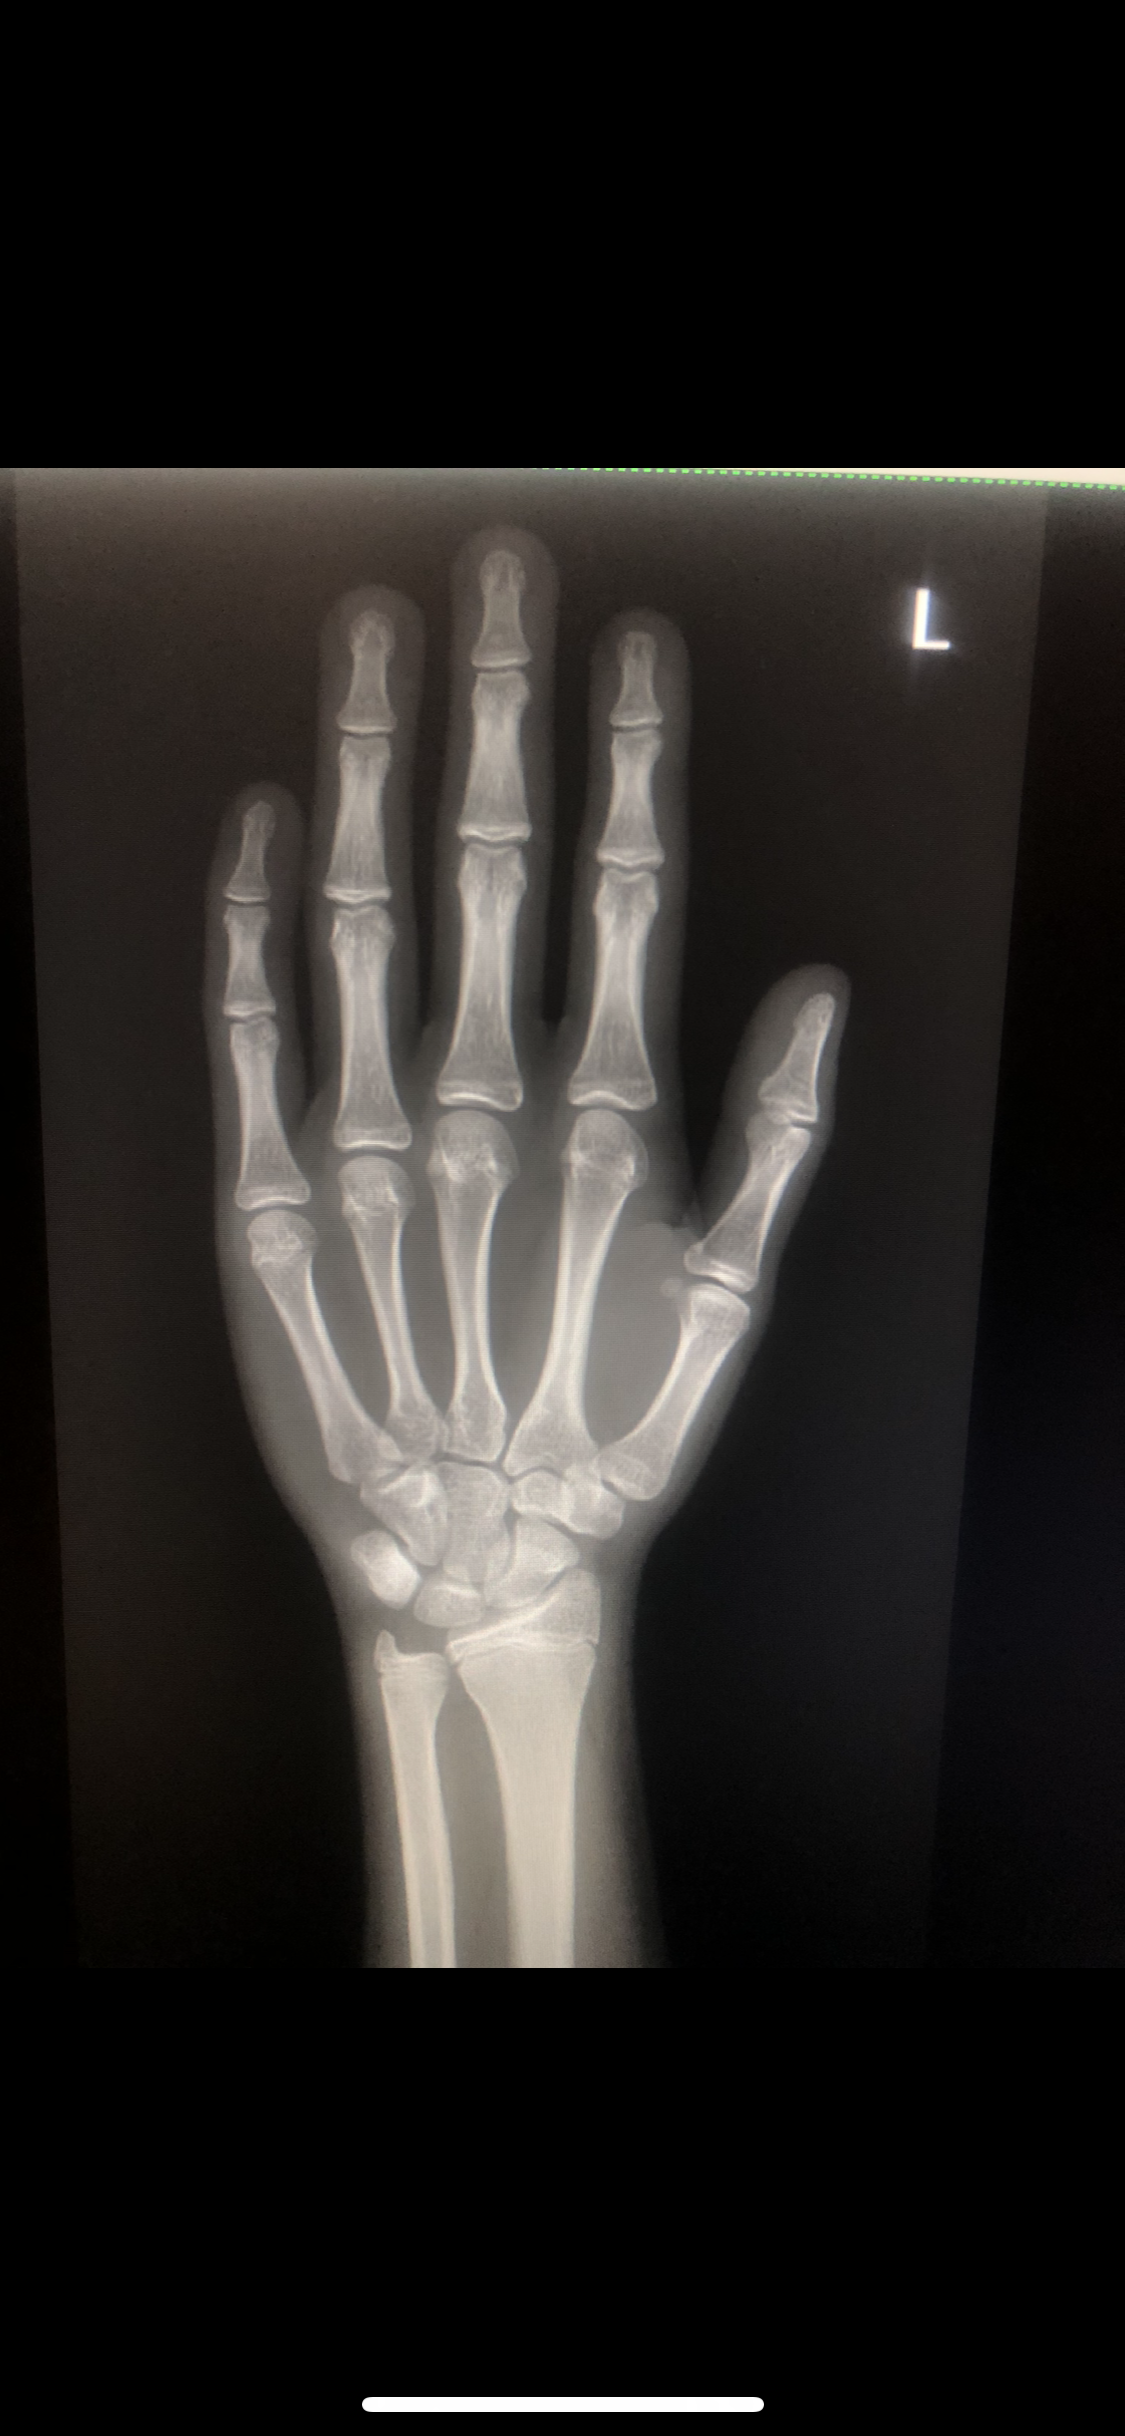

So. Igot diagnosed too late that im ghd and my plates are fusing and doc prescribed 6 ius daily and he said i wouldve prescribed u ai if u came at 14 :feelsrope::feelsrope:

IMG 2301